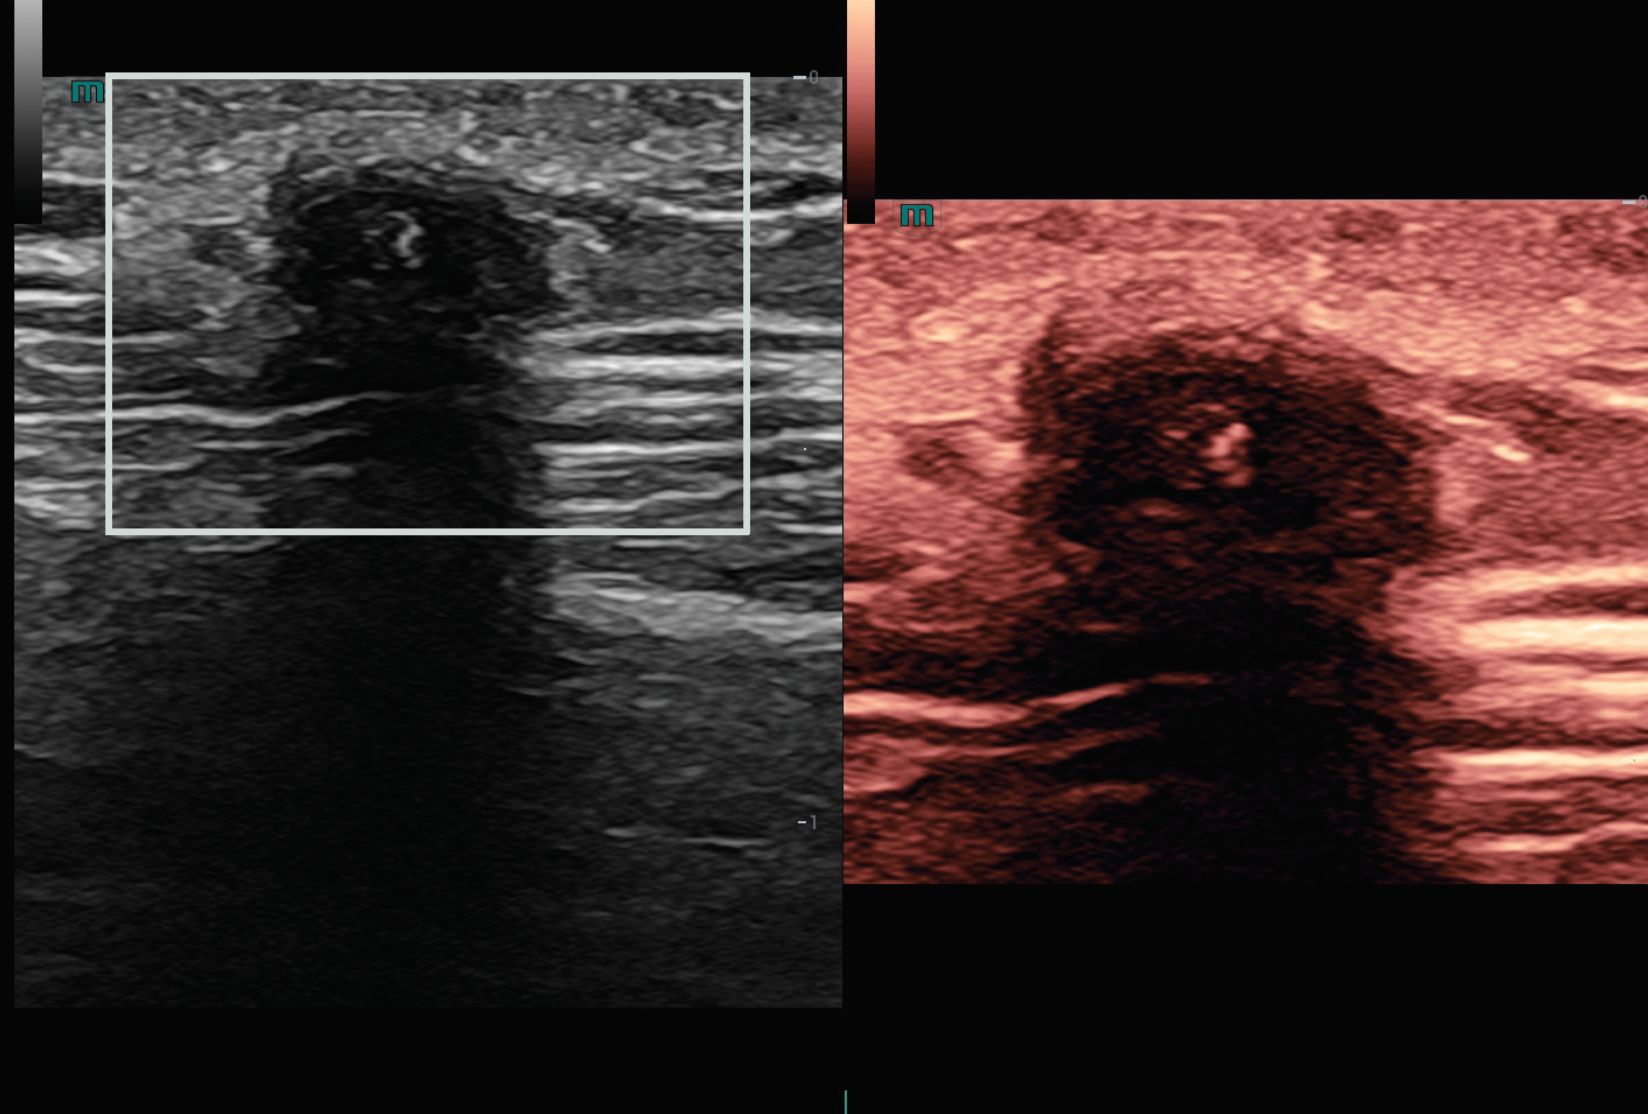

A closer look at just a few of our transducers: